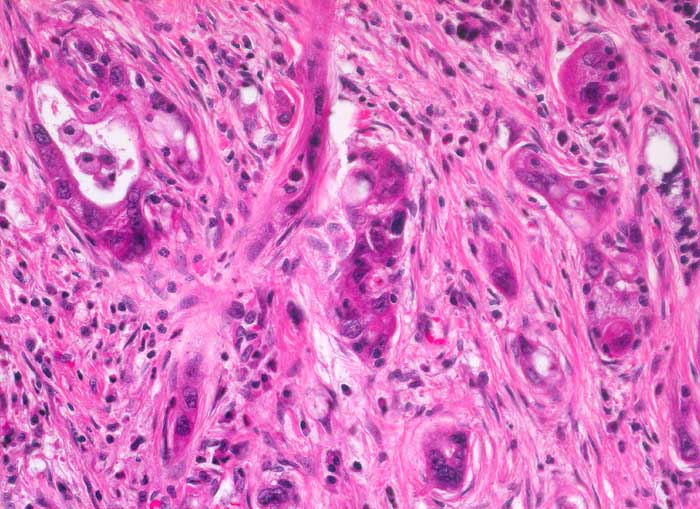

Die meisten Pankreaskarzinome sind mässig bis hoch differenziert und führen zu einer deutlichen desmoplastischen Stromareaktion (derbe Konsistenz). Hochdifferenzierte Tumoren (> 1502) können sehr ähnlich aussehen wie eine chronische Pankreatitis (> 4243). Im Gegensatz zur Pankreatitis sind die neoplastischen Drüsen verformt oder rupturiert und zeigen zelluläre Atypien (grosse polymorphe Kerne mit prominenten Nucleolen). Die Tumordrüsen sind unregelmässig im Stroma angeordnet und nicht lobulär wie in der Pankreatitis. Nicht selten ist eine Nervenscheideninvasion nachweisbar (> 5884). Gelegentlich zeigen die Gänge im tumorfreien Parenchym dysplastische Veränderungen oder der Tumor breitet sich intraduktal entlang des Pankreasganges aus.

Morphologische Merkmale:

• Unregelmässige Anordnung der Drüsen (keine Läppchenarchitektur erkennbar).

• Kribriforme Drüsenformationen.

• Inkomplette Drüsen mit unvollständigen Lumina und Infiltration des Stromas durch Tumoreinzelzellen.

• Nekrotische Tumorzellen in den Drüsenlumina.

• Ausgeprägte Polymorphie und Hyperchromasie der Tumorzellkerne.

• Desmoplastisches Stroma.